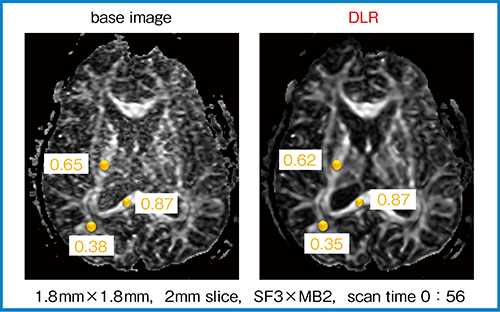

定量評価においても,DLR処理によるノイズ除去は有用であると考えている。例えば,元画像から作成したFA(fractional anisotropy)マップはSNRが非常に低いが,DLR処理を行うことでノイズの少ない画像が得られる(図5)。ROI内のFA値を計測すると,平均値はそれほど変わらないが,SDがかなり小さくなっているため,定量評価における精度向上が期待できる。

図5 定量評価におけるDLRの有用性(W.I.P.)